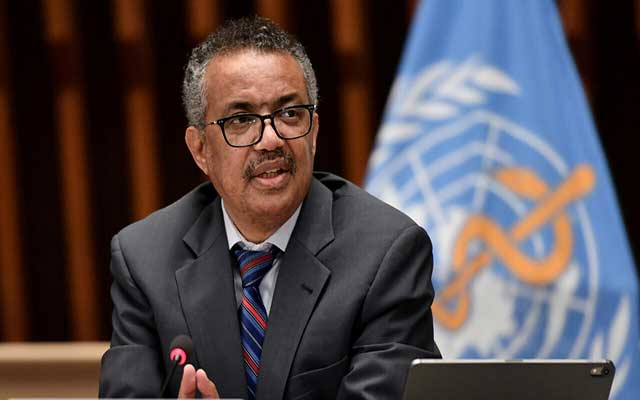

وقال مدير إدارة الحوادث في المنظمة عبدي محمود، إن مزيدا من الأدلة تظهر أن "أوميكرون" يصيب الجهاز التنفسي العلوي، لكنه يسبب أعراضا أخف من المتحورات السابقة.

وردا على سؤال حول ما إذا كان "أوميكرون" سيحتاج إلى لقاح خاص، أوضح محمود أنه "من السابق لأوانه تحديد ذلك"، لكنه أكد أن هذا القرار يحتاج إلى تنسيق عالمي ولا يجب أن يتخذه القطاع التجاري وحده.